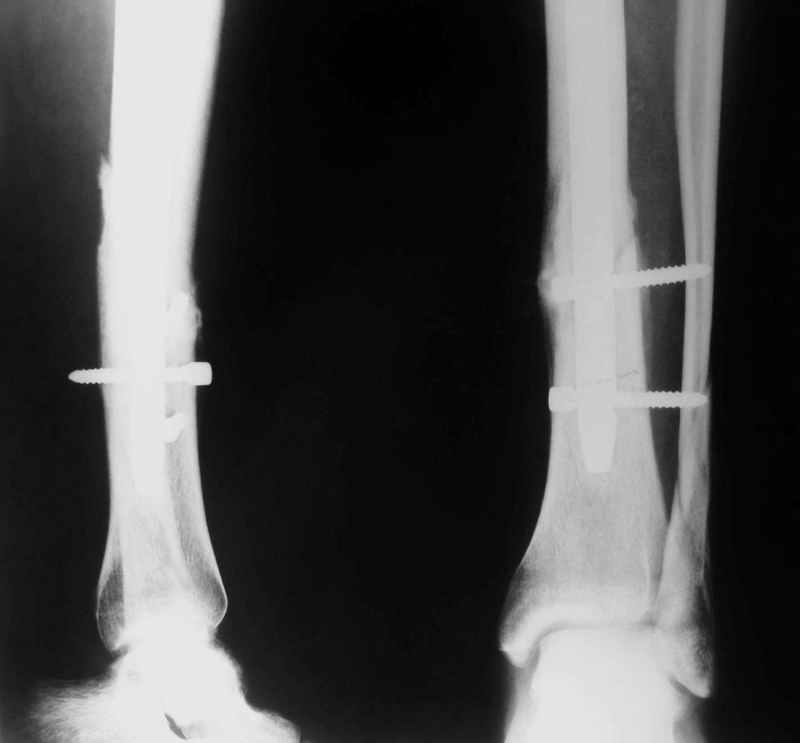

В 2002 г. была у нас больная с ложным суставом бедра и остеомиелитом (как оказалось), после удаления пластины. Гвоздь с блокированием.

Потекло через месяц - открылось 2 свища по старому рубцу от давно удаленной пластины. На фоне гноя раза три завинчивал обратно винты, которые вылезали латерально, прямо через свищ. Потом таки провел дополнительно винты мимо гвоздя, и убрал вверху статический винт. Острый гнойный процесс стих, свищи мыла она дома дважды в день водным хлоргексидином, ходила с возрастающей нагрузкой, а к 10 мес. и свищи закрылись, и срослось. Итоговые снимки от 18 апреля 2003 г. прилагаю.

Перелом спиральный, то есть низкоэнергетический, так что со сращением дело обстоит уже неплохо, лишь бы "костоеда" не развилась. Отломки выглядят уже стабилизированными костной мозолью, так что довводить винты, наверно, уже незачем. Разве что при клинической оценке подвижность еще есть - тогда можно для стабилизации наложить простейший аппарат, не опасаясь контакта его элементов с гвоздем, поскольку места в дистальном метафизе оставлено более чем достаточно.